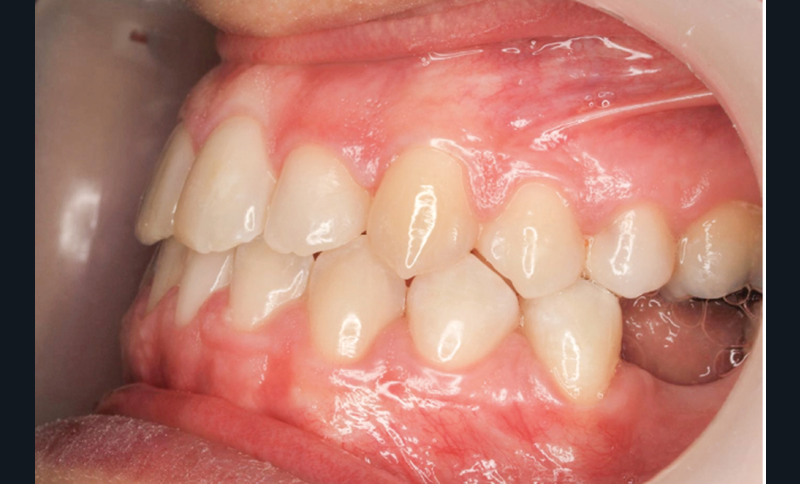

Diagnostic (fig. 1a-g)

La patiente présente une classe III squelettique dans un contexte hyperdivergent associée à une endoalvéolie maxillaire, un articulé inversé antérieur, une rétroversion incisive maxillaire, des rapports de classe I canine bilatérale, une absence de 16 et 36.

Au niveau esthétique, le profil est rectiligne. La lèvre supérieure est plus effacée, en retrait par rapport à la lèvre inférieure. De face et de profil, la mandibule paraît massive et le maxillaire effacé : le manque de soutien de la lèvre supérieure contribue à cette impression.

Le sourire est étroit, dégradé par les malpositions dentaires.

Au niveau fonctionnel, il existe un pro-glissement mandibulaire et un articulé inversé antérieur. Le profil téléradiographique montre en occlusion des rapports labiaux et un profil de classe III plus marqué que sur photographies.